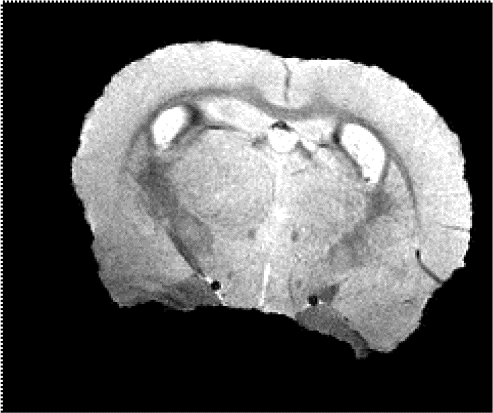

Figure 1. All fifteen mice survived the in-vivo imaging before being euthanized. Representative images of a control mouse and +/+ mouse at 12 months old are shown.